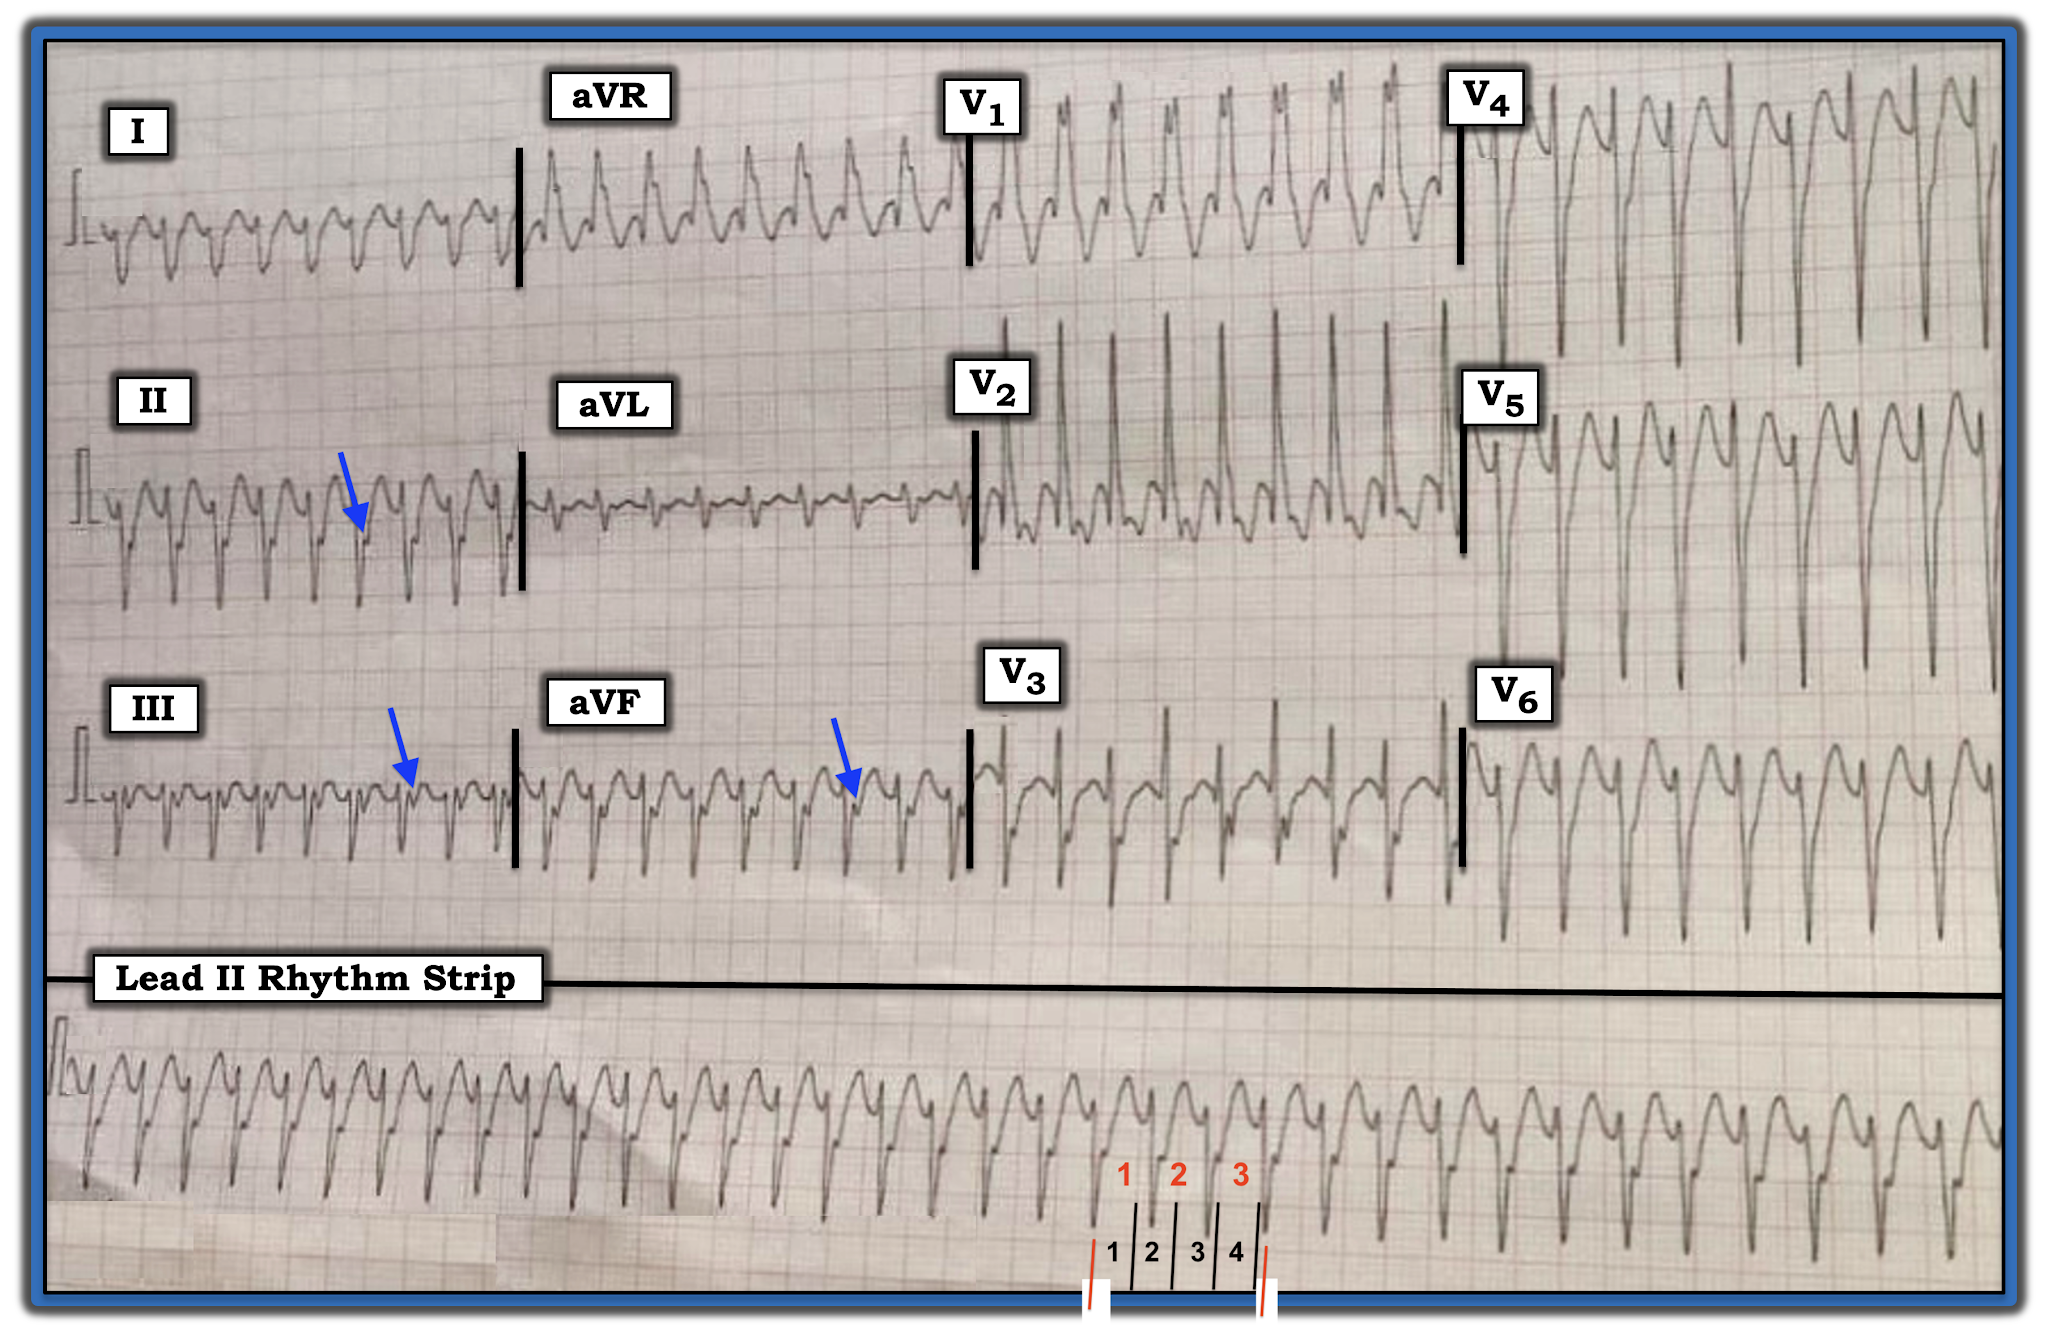

The ECG in Figure-1 was obtained from a 30-year-old man with palpitations. He was hemodynamically stable at the time this tracing was done.

| Figure-1: ECG obtained from a 30-year-old man with palpitations (See text). |

Unfortunately, the 12-lead ECG with long lead II rhythm strip shown in Figure-1 is “technically challenged” (ie, slanted). That said — I believe the quality of this tracing is still adequate for accurate rhythm assessment. By the “Ps, Qs & 3R Approach” that I favor (Reviewed in ECG Blog #185):

- The QRS complex is wide (clearly more than 3 little boxes = >0.12 second in duration).

- Normal sinus P waves are absent (ie, there is NO clear sign of upright P waves in lead II — See Pearl #2 below).

- There are therefore no sinus P waves that might be Related to neighboring QRS complexes.

- The rhythm is Regular (ie, despite the slant of the tracing — the QRS complex remains regular throughout the long lead II rhythm strip).

Finally, regarding the 5th Parameter in the Ps, Qs & 3R Approach — I estimate the Rate of the rhythm in Figure-1 to be ~210/minute.

- To estimate this — I used the Every-Third-Beat Method (Figure-3). I began by selecting a QRS complex for which the deep negative point of the QRS fell precisely on a heavy grid line (See the 1st vertical RED line in the long lead II under this beat).

- The amount of time that it takes to record 3 beats (RED numbers in the long lead II) is just over 4 large boxes (BLACK numbers in Figure-3). Therefore — ONE THIRD the rate is a little slower than 300/4 ~70/minute.

- Therefore — the actual rate for the rhythm in Figure-3 is ~70 X 3 ~210/minute.

PEARL #2: I can not rule out the possibility that the negative deflection seen in each of the 3 inferior leads at the end of the QRS complex in Figure-3 (BLUE arrows) might represent retrograde atrial activity. That said, even IF this was retrograde 1:1 VA conduction — this would not help diagnostically, because both VT and reentry SVT rhythms may manifest 1:1 VA conduction.

- After conversion to sinus rhythm — we’ll be able to tell IF this negative deflection did indeed represent retrograde atrial activity (IF it did — then this negative deflection highlighted by the BLUE arrows in Figure-3 should no longer be present once sinus P waves return).

By the Ps, Qs & 3R Approach — we have defined a regular WCT (Wide-Complex Tachycardia) Rhythm at ~210/minute, without clear sign of sinus P waves.

Regarding QRS Morphology in Figure-3:

QRS morphology for the regular WCT rhythm in Figure-3 resembles RBBB — because there is a wide, predominant positive QRS complex in lead V1 — with wide terminal S waves in lateral leads I and V6. That said — there are several atypical features that to me strongly suggests that this rhythm is likely to represent a form of Fascicular VT. The atypical features in QRS morphology include:

- Although QRS morphology in lead V1 of Figure-3 is wide and predominantly positive — there is no initial r wave and, the R’ deflection is both very wide and notched (whereas with typical RBBB morphology — the R’ deflection is usually thinner and not notched).

- There are anterior Q waves (seen here in leads V1 and V2) — whereas this is usually not seen with typical RBBB morphology unless there has been prior anterior infarction (which is clearly less likely to have occurred in a previously healthy 30-year-old).

- The frontal plane axis is indeterminate (ie, there is predominant negativity in leads I, II and III). Neither of the hemiblocks normally manifest predominant negativity in all 3 of the standard limb leads (whereas this pattern is not uncommon with fascicular VT).

- BOTTOM LINE: At the time that I wrote this post, I did not yet have follow-up in this case — so I do not yet have a definitive answer. That said — given that the patient is a presumably previously healthy 30-year-old man (therefore, unlikely to have a baseline ECG showing preexisting RBBB with an atypical QRS morphology) — I thought the rhythm for the ECG shown in Figure-3 was most likely Fascicular VT. I would treat the patient accordingly (ie, with initial trial of IV Verapamil, given that the patient is hemodynamically stable).